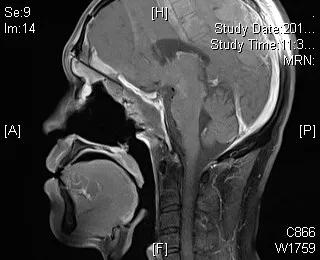

我院耳鼻喉科时光刚主任率领的鼻颅底外科团队,在神经外科许尚臣主任医师,麻醉科王公明主任医师以及护理人员胡姗姗等的支持下,成功实施手术。目前,患者术后已2月余,复查颅脑MRI提示肿瘤彻底切除,内镜检查提示鼻颅底缺损愈合好。

手术后影像